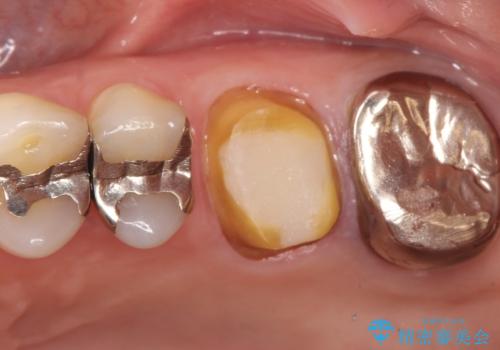

【再根管治療】オールセラミッククラウンによる修復

- 治療途中の歯があることを主訴に来院されました。

根管治療を行なったのちオールセラミックにて修復治療を行なっております。

第二大臼歯の治療は希望されませんでした。